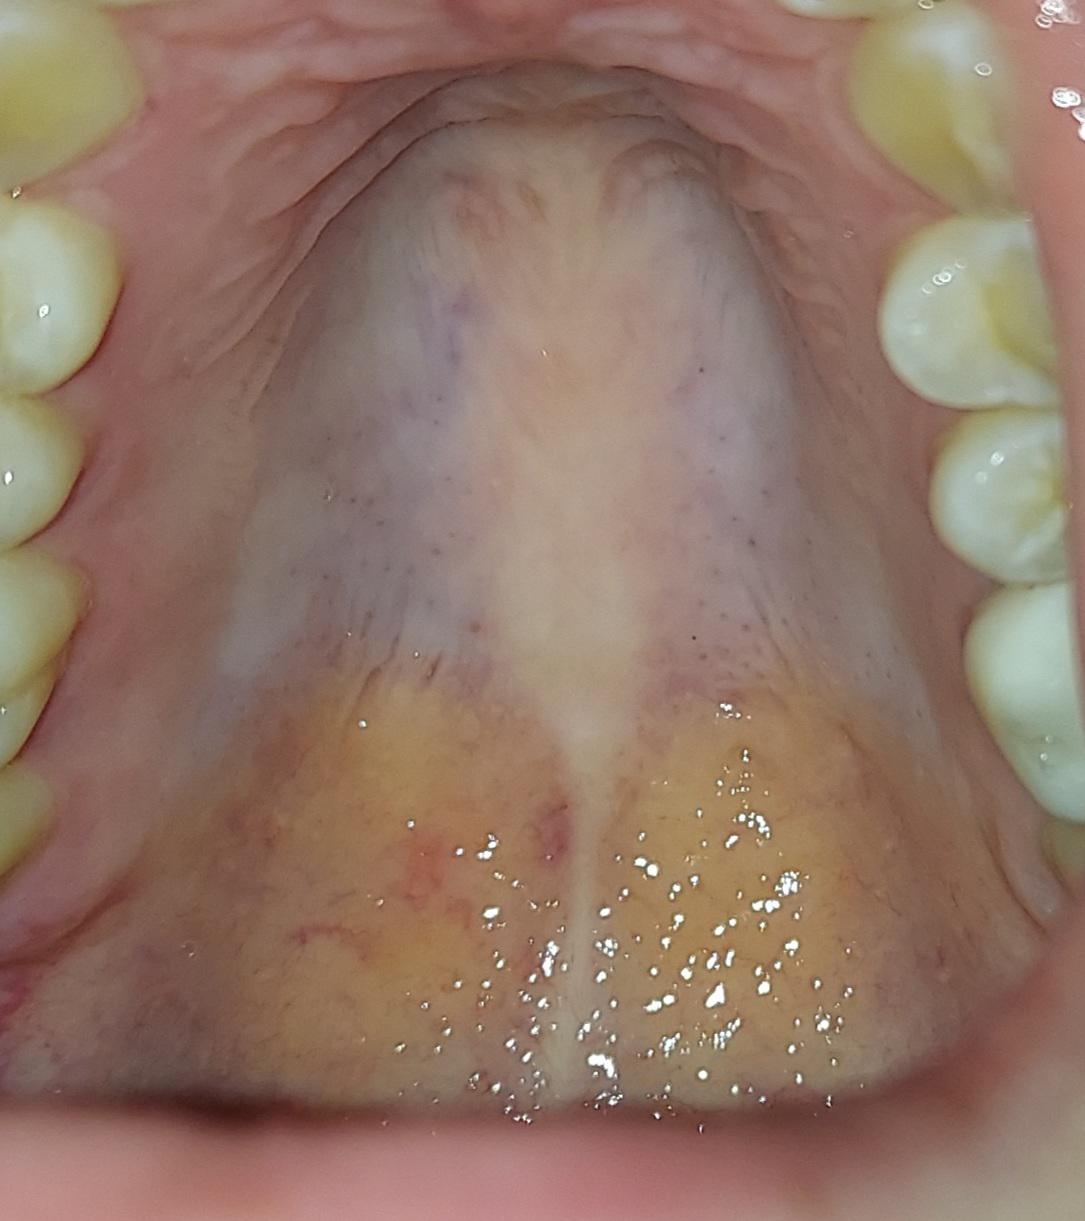

Palate Expander Before And After

Discover the benefits of palate widening orthodontics for correcting narrow arches and improving dental alignment. Our expert guide explains how palatal expansion appliances work to resolve overcrowding, enhance breathing, and achieve a broader, healthier smile for both children and adults. Learn how this effective orthodontic treatment creates optimal space for proper bite function and long-term oral health.